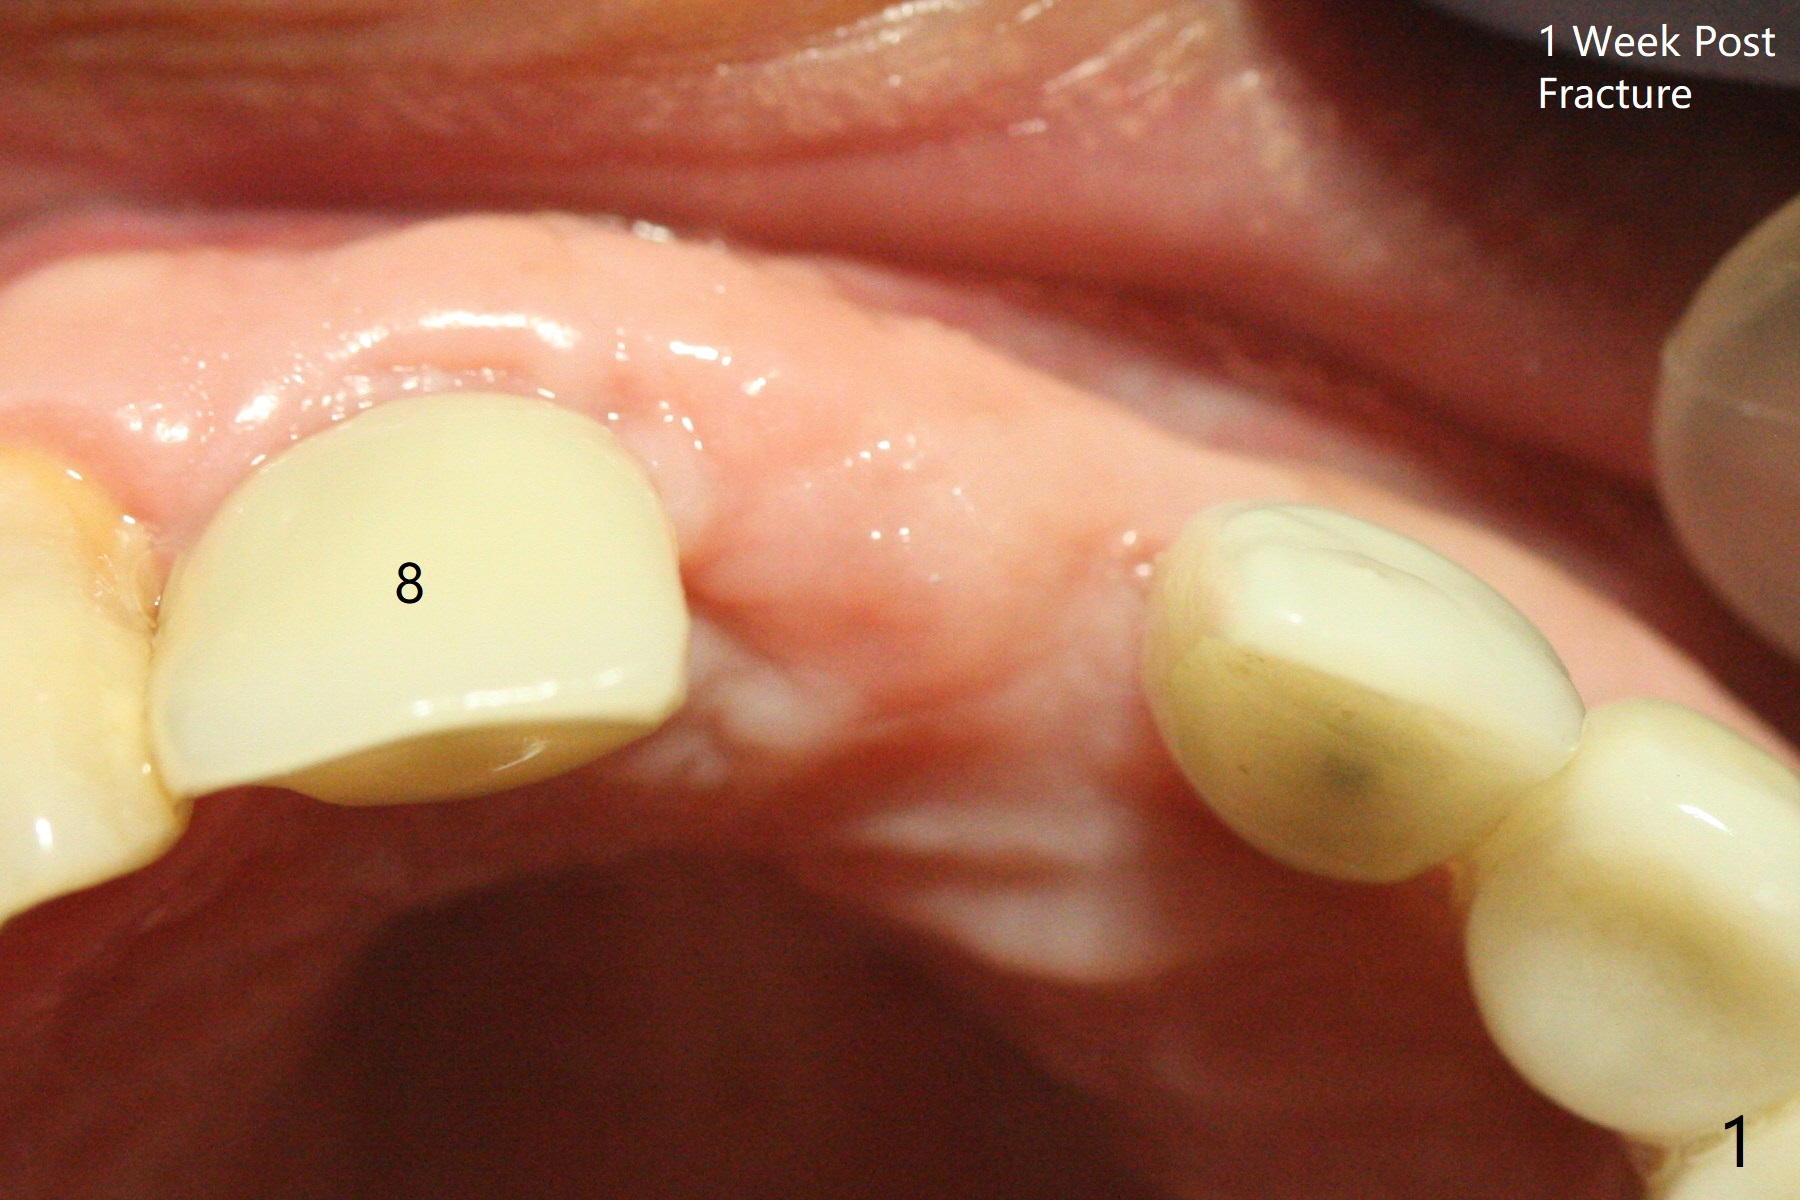

The implant access at #9 closes 1 week post implant fracture (Fig.1,4). There is mild gingival erythema at #10 (Fig.2,3 ^). There is bone around the fractured implant, which is palatally placed (Fig.5). The 2 mm implant is removed using 2/3 mm trephine bur. In spite of moving the osteotomy buccally, a 4.5x4 mm, 15 degree A-type angled abutment is installed for an immediate provisional following placement of a 3.5x10 mm implant (Fig.7, 25 Ncm). Sticky bone is placed (Fig.7 *) palatal to the implants at #9 and 10 (with thread exposure, Fig.6). While the majority of periodontal dressing remains in place (Fig.9,10), the suture in the exposed area appears to hold the papilla in place (Fig.8 <). Herpetic infection develops in the palate (Fig.9). Two months later, the gingiva at #10 is healthy; it appears that the implant threads are covered by bone graft. The immediate provisional (fabricated before suture) keeps the gingiva in an ideal position for impression of final restoration. It appears that the access hole is in a right area for screw retained restoration. The gingival cuff is healthy immediate pre-cementation, 4 months postop (Fig.12,13). The lab does not make access hole for the final crown (Fig.14). The implant remains subcrestal 4 months postop (Fig.15). Since the shade of the crown is off, the abutment remains un-torqued and the crown is cemented with temp bond. The implant threads at #10 seem to be covered by bone graft 4 months postop (Fig.16).